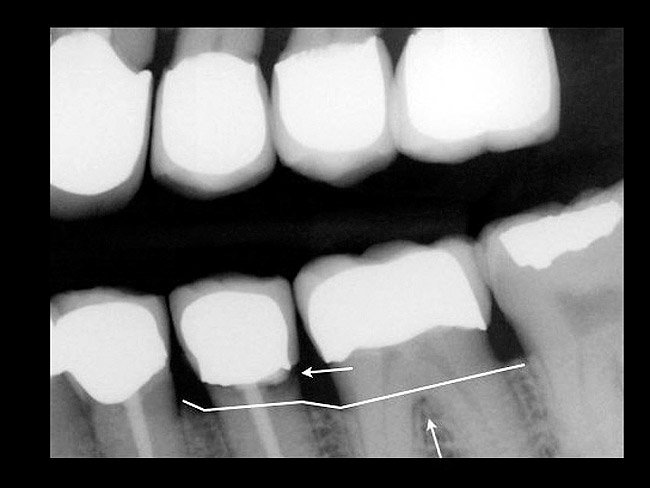

Bone defect morphology plays an important role in the predictability of tooth retention as well. Horizontal defects are unpredictable to guided tissue regeneration attempts (Figure 8). Narrow vertical defects respond more favorably to regeneration attempts (Figure 9).21